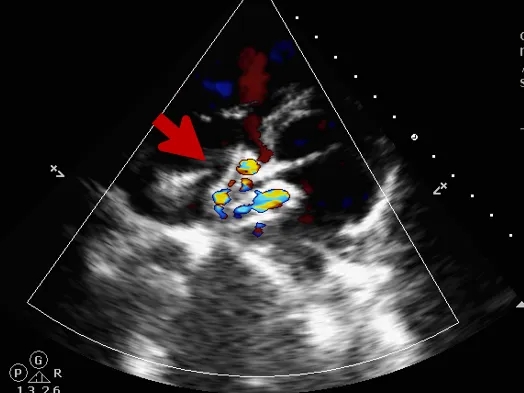

锁定后评估

心尖四腔心切面可见封堵器形态良好

主动脉短轴切面可见封堵器呈“Y”字型抱住主动脉

彩色多普勒血流成像显示无残余分流存在

释放后评估

封堵器位置正确、形态良好

封堵成功